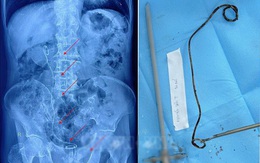

Ống sonde hơn 20cm 'ngủ quên' trong thận - bàng quang cụ ông 82 tuổi

Bệnh viện Đại học Nam Cần Thơ vừa phẫu thuật thành công lấy dị vật là ống sonde JJ dài hơn 20cm ra khỏi thận - bàng quang cho cụ ông 82 tuổi từ Sóc Trăng.